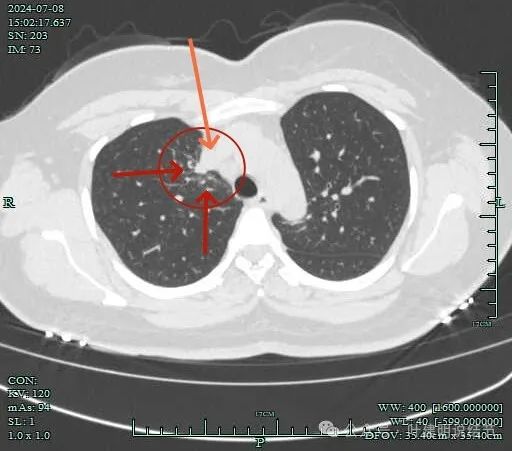

邻近支气管有扩张,表面不平,分叶明显。

肺窗上见与上腔静脉紧贴着,病灶边缘稍显模糊。

病灶边上不清爽。

病灶有毛刺与小棘突征,有邻近细支气管扩张,表面不平,膨胀性不明显。

毛刺征明显,灶边细支气管扩张。